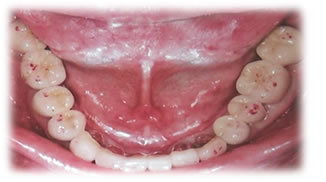

顎関節に適した咬み合わせにするために、仮歯(プロビジョナルレストレーション)を装着して咬み合わせから治療する方法。

顎の位置の確認(CT撮影) - 安定後メタルスプリントの作成もしくはプロビ作成

→装着期間 約1か月